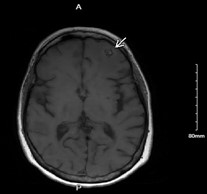

Clinical History: 66-year-old female with presents with seizures and progressive enlargement of anterior cranial fossa presumed meningioma with increased surrounding vasogenic edema approximately 4 years after Gamma Knife surgery.

Radiology: Extra axial lesion along the anterior inferior left frontal convexity, demonstrates some mild intrinsic T1 and T2 hyperintense signal, mostly T2/FLAIR hypointense with prominent susceptibility artifact. Moderate amount of T2/FLAIR hyperintense signal within the white matter of anterior and inferior left frontal lobe.